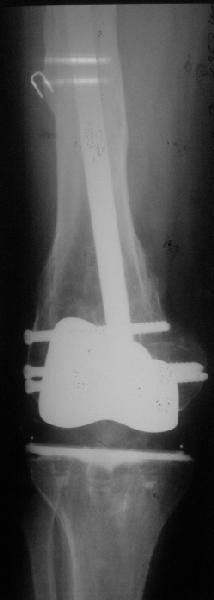

Видимо, самое "модное" на сегодня - малоинвазивный остеосинтез пластиной с угловой стабильностью. Распространенный вариант и закрытый интромедуллярный остеосинтез ретроградно. Хотя у нас было бы сделано антеградно - лешево и сердито, действительно малоинвазивно, в сустав не надо влезать. Нет риска прорезания порозной кости с миграцией в сустав, что возможно при ретроградном - гвоздь вводится через вырез в бедреннм компоненте, туда же может и вывалиться. А антеградный - упрется в протез. Как раз вчера заходил больной через полтора года после такой операции. Снимки в приложении.